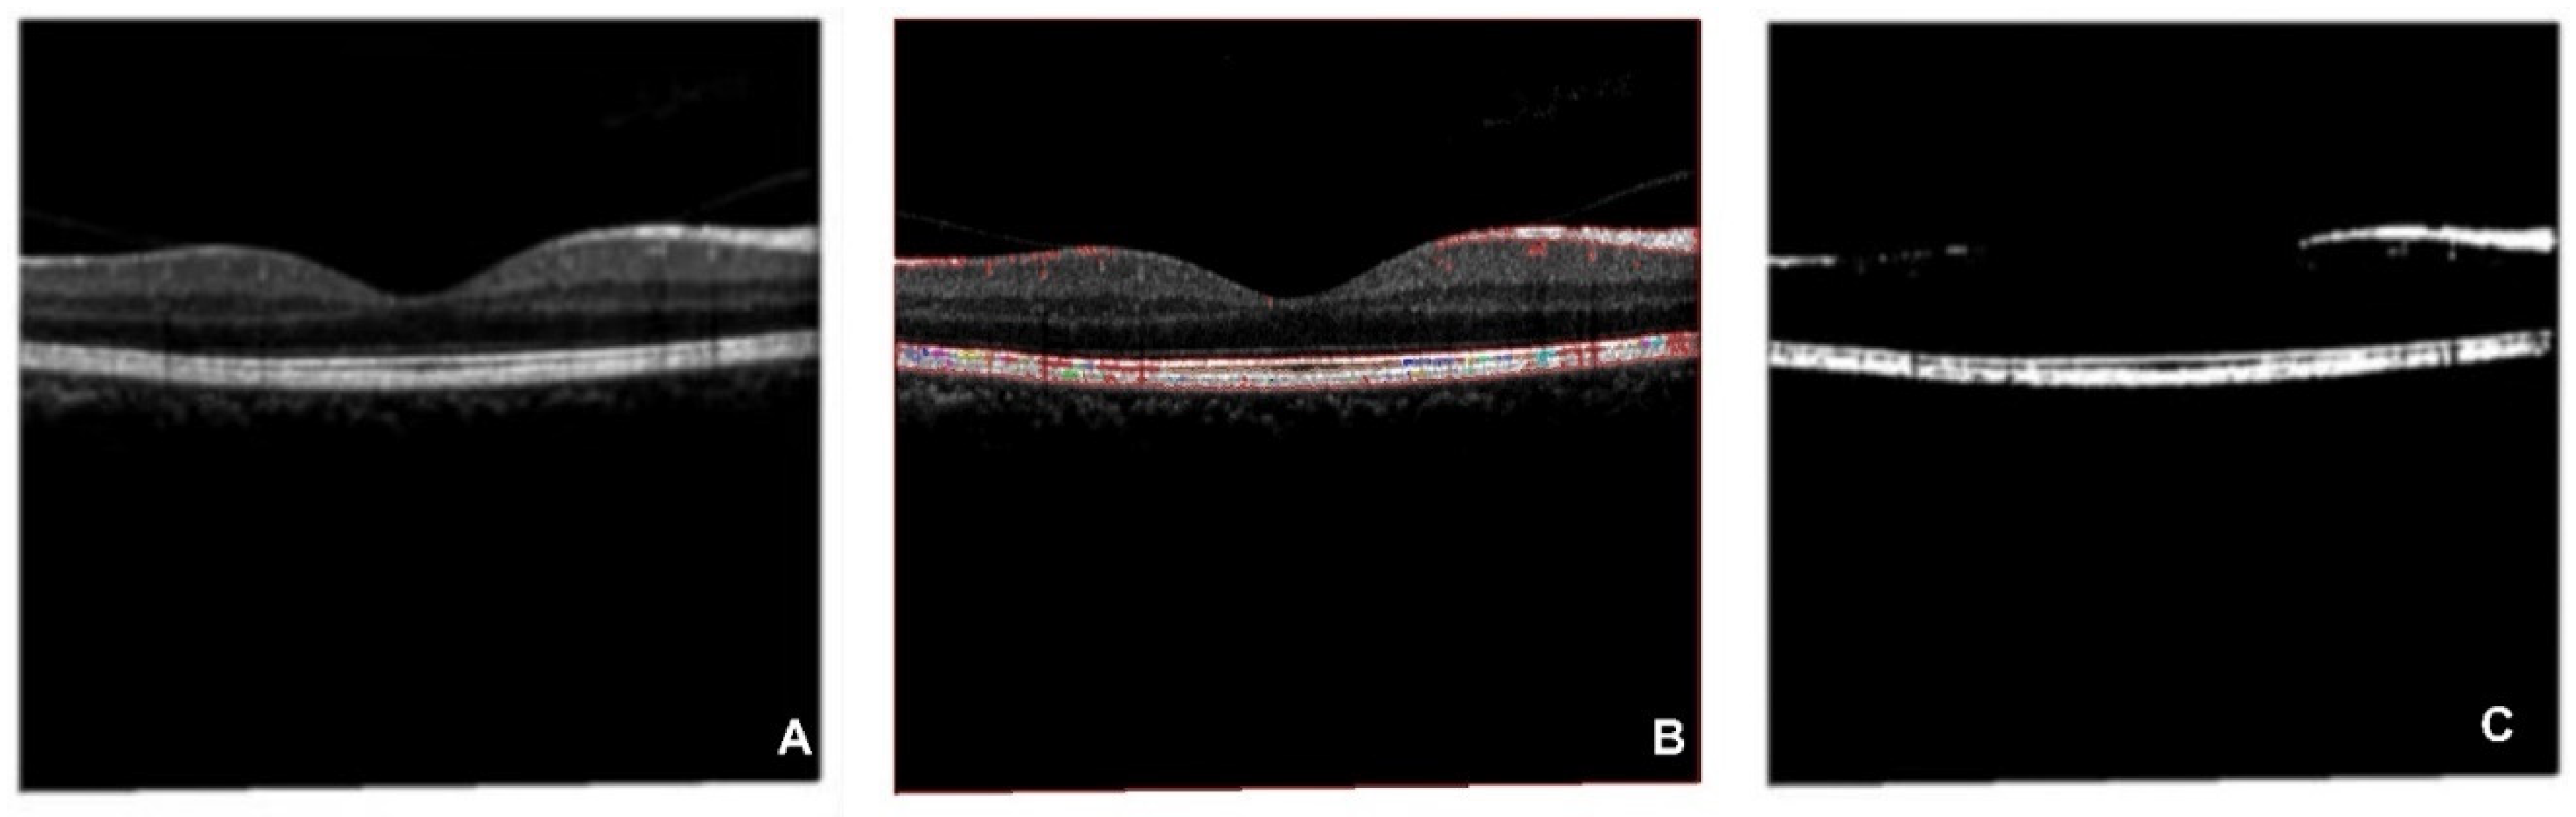

Figures in the OCT database are processed by the CFS algorithm to extract key features, which are output as an OCT-segmented database (

Figure 9). The CFS algorithm has been widely applied to multiple medical images preprocesses[66, 67]. As

Figure 9 shows, subfigure A is the original figure, B is related to image feature identification, and C is the segmented OCT image. Shapes of the macular epiretinal membrane and choroid are extracted with smooth edges (white part shown in C).

Figure 9.

CFS process on OCT database (A is the original figure, B is related to image feature identification by CFS, C is related to the segmented OCT image).